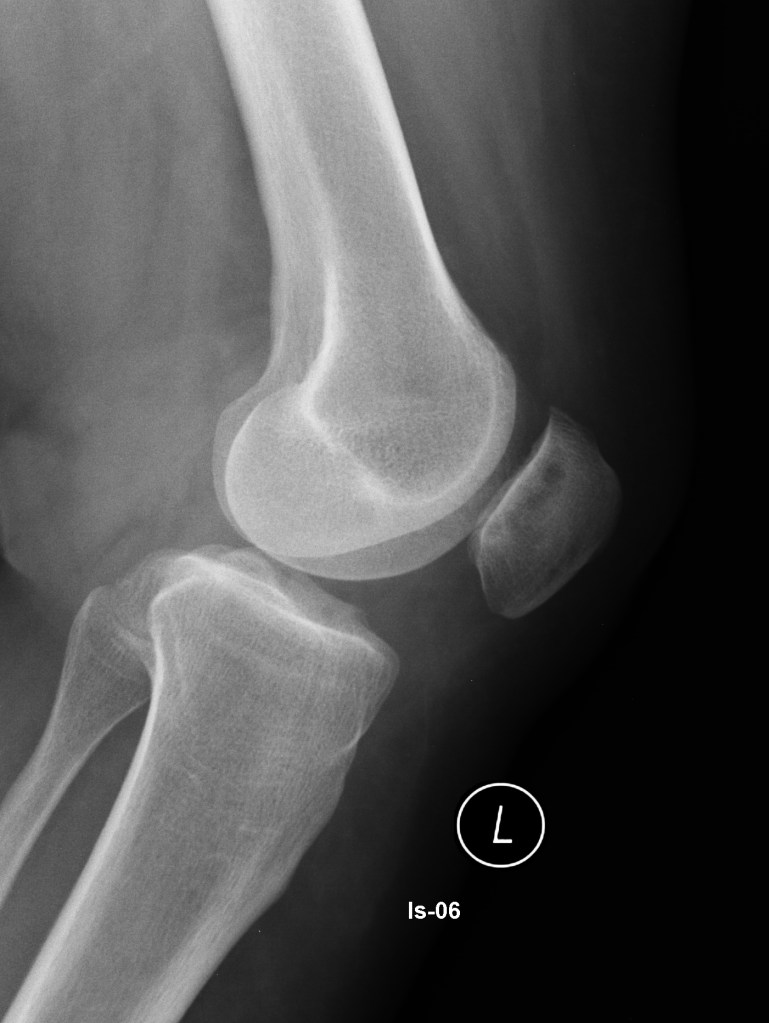

- Radiografia: Embora a cartilagem em si não apareça na radiografia, esse exame ajuda a descartar outras causas de dor, como fraturas, artrose ou desalinhamentos ósseos que podem estar associados.